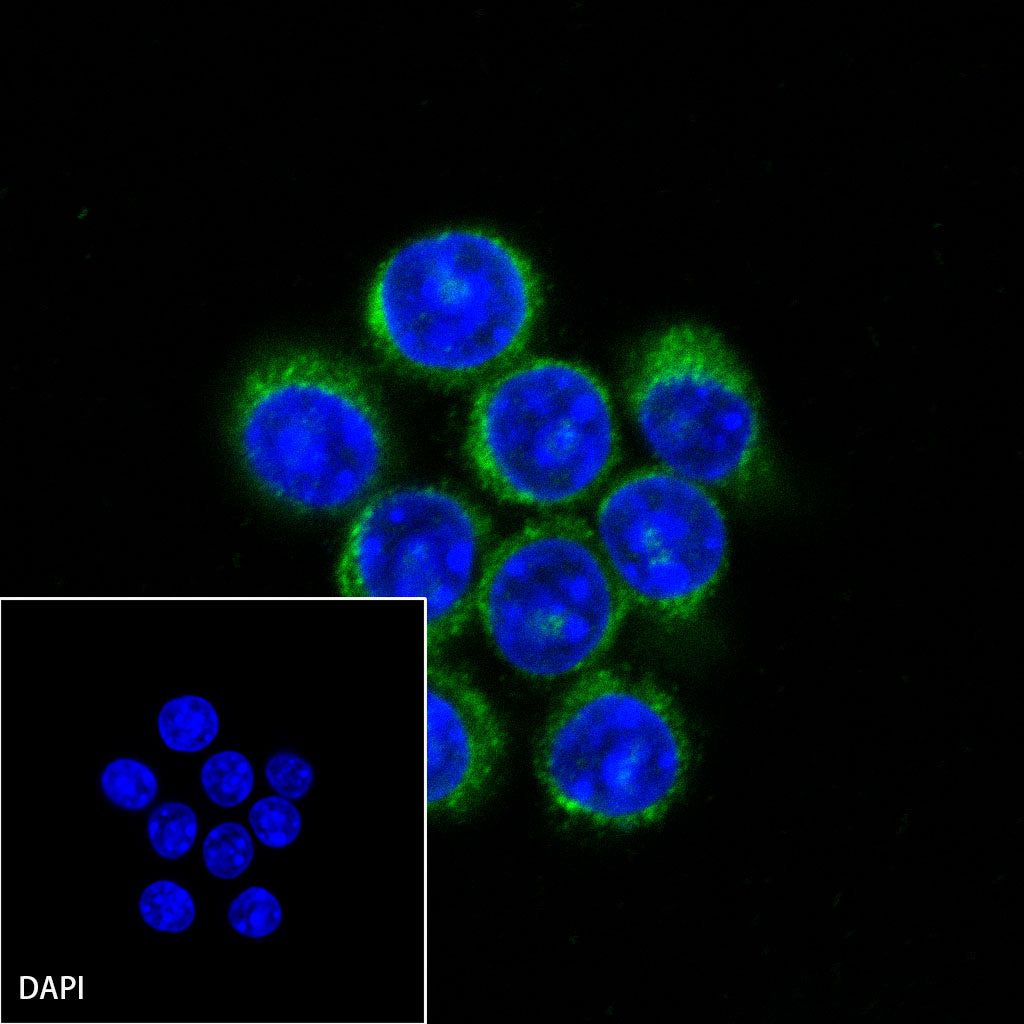

Immunocytochemistry

ICC shows positive staining in RAW264.7 cells. Anti-CD68 antibody was used at 1/250 dilution (Green) and incubated overnight at 4°C. Goat polyclonal Antibody to Mouse IgG - H&L (Alexa Fluor® 488) was used as secondary antibody at 1/1000 dilution. The cells were fixed with 100% ice-cold methanol and permeabilized with 0.1% PBS-Triton X-100. Nuclei were counterstained with DAPI (Blue).